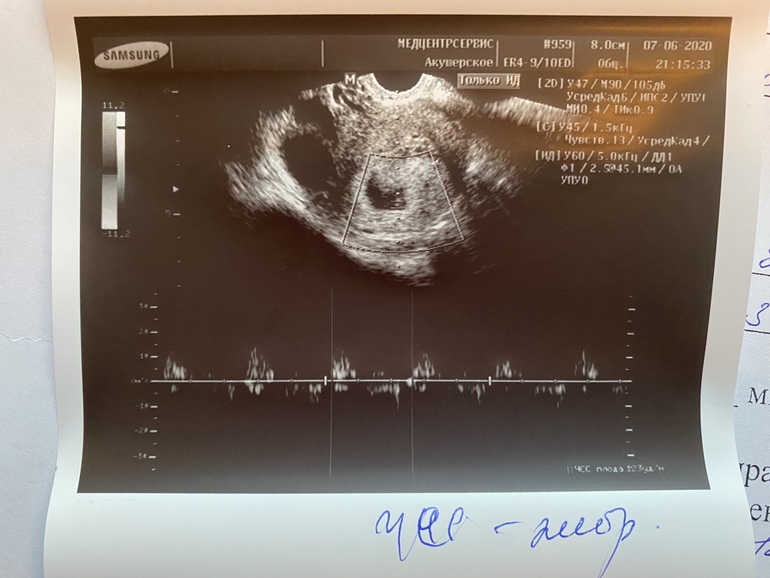

В общем, пока я в панике соображаю как сейчас в 9 часов вечера купить ампулы и найти врачей, которые поставят капельницу на дому, иду в туалет... и тут понимаю что все... приехали! На толчке из меня льет кровь и просто вываливается кусок!! Не кусочек, а кусок! С мою ладонь, тонкая такая, как кусок печени, еще чуть полило и все! Тут же кровить перестала. Я думала, что это собственно оно.... все произошло, если вы поняли о чем я. Фото своих трусов и этого куска я отправила Ре, она сказала это в баночку в физ раствор и холодильник, а мне бы сделать срочное узи. Я уже ни во что не верила, нашла круглосуточное узи рядом с домом, через пять минут была у врача... И вот бывает же так, когда в такие моменты рядом оказываются хорошие люди. Я ни жива ни мертва, на подкашивающихся ногах, легла на кушетку... а она смотрит и говорит... "Зайчик, не волнуйся, все нормально, вот твой эмбрион, вот у тебя гематома какая", включила СБ, я его слышала! 123 удара в минуту, КТР 4,7, ЖМ 3 мм, ПЯ 30 мм. Но гематома есть, на фото узи эндометрий такой разрыхленный... сейчас приложу фото...